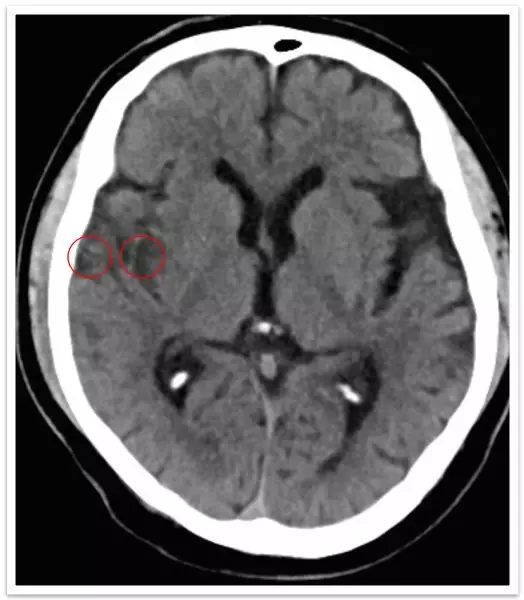

病例概要 基本信息:56岁,男性。 主诉:言语不利、左侧肢体无力7.5小时,加重3.5小时。 查体:神清,言语不利,双侧瞳孔等大正圆,双眼向右侧凝视,左侧中枢性面舌瘫,左侧上肢肌力I级,左下肢肌力III级,左侧下肢针刺痛觉减退,左侧病理征阳性。NIHSS评分:10分。 既往史:高血压,吸烟史多年。 术前影像:急诊CT平扫可见右侧颞叶及M2区低密度改变。

影像学表现与临床症状不匹配,发病超7小时。 DSA: 右侧颈内动脉C1段闭塞;右侧大脑中动脉M1段闭塞,颈外动脉经眼动脉向颅内代偿。